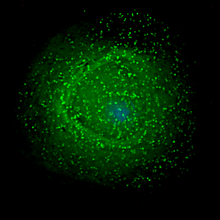

HIV assembling on the surface of an infected macrophage.

The final step of the viral cycle, assembly of new HIV-1 virions, begins at the plasma membrane of the host cell. The Env polyprotein (gp160) goes through the endoplasmic reticulum and is transported to the Golgi complex where it is cleaved by furin resulting in the two HIV envelope glycoproteins, gp41 and gp120. These are transported to the plasma membrane of the host cell where gp41 anchors gp120 to the membrane of the infected cell. The Gag (p55) and Gag-Pol (p160) polyproteins also associate with the inner surface of the plasma membrane along with the HIV genomic RNA as the forming virion begins to bud from the host cell. The budded virion is still immature as the gag polyproteins still need to be cleaved into the actual matrix, capsid and nucleocapsid proteins. This cleavage is mediated by the also packaged viral protease and can be inhibited by antiretroviral drugs of the protease inhibitor class. The various structural components then assemble to produce a mature HIV virion. Only mature virions are then able to infect another cell.